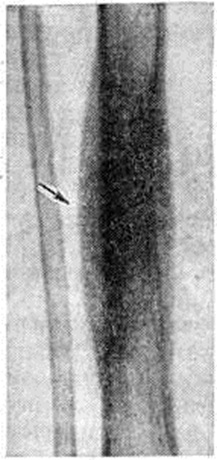

Рис. 2. Макропрепарат большеберцовой кости при остеомиелите после огнестрельного ранения: в зоне сросшегося перелома виден гнойник с мелкими секвестрами (один из них указан стрелкой).

В других случаях наблюдается инкапсуляция гнойников в кости. К 3—4-й недель от начала заболевания при рентгенологическое исследовании на фоне рарефикации определяются очаги некроза кости, поскольку омертвевшая кость не подвергается резорбции и сохраняет прежнюю плотность. При патологоанатомическом исследовании участки некроза выявляются ещё раньше. В дальнейшем те из них, которые находятся в самом очаге нагноения, подвергаются секвестрации (рисунок 1). Секвестрация (смотри полный свод знаний Секвестр, секвестрация) заключается в отторжении омертвевших участков кости, находящихся в полости гнойника, от окружающей костной ткани. При этом в случае образования секвестра в компактной пластинке на её поверхности в зоне прилегания грануляций возникает и постепенно углубляется секвестральная борозда, а в толще — расширение гаверсовых каналов и слияние их между собой. После того как все костное вещество в указанной зоне растворится, секвестр оказывается свободно лежащим в полости гнойника (цветной рисунок 2 и 3). Секвестры губчатого вещества кости отделяются от остальной её части за счёт растворения прилежащих костных балок, находящихся в зоне грануляций (рисунок 2).